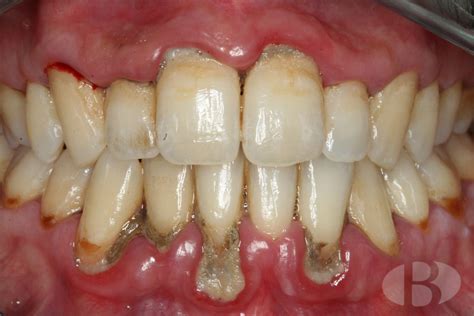

Imagen real de un caso avanzado de periodontitis.

Las bolsas periodontales son espacios o surcos profundos que se forman entre los dientes y las encías debido a la acumulación de placa y bacterias.

Las bolsas periodontales, si no se tratan, pueden causar dolor, infección, y eventualmente, la pérdida de dientes. Una bolsa de pus en la encía indica una infección seria. Una bolsa periodontal de 7 mm indica una periodontitis avanzada.